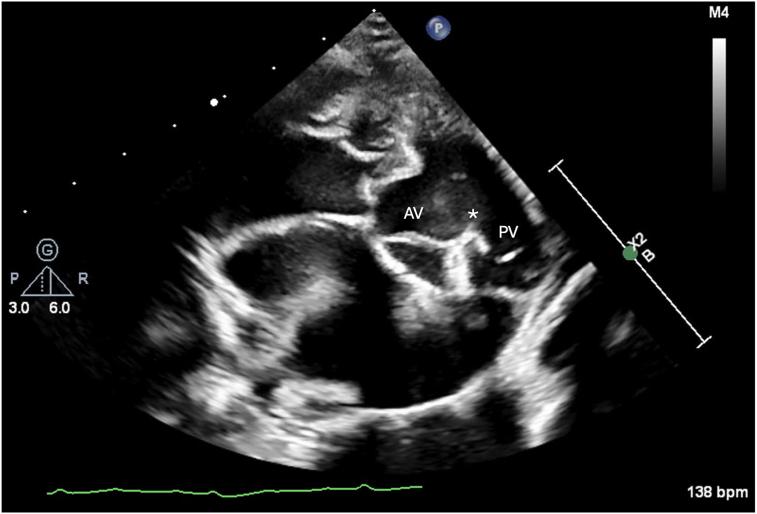

Multimodal Imaging Diagnosis of Doubly Committed Juxta-Arterial Ventricular Septal Defect and Persistent Left Cranial Vena Cava in a Goat.

CASE (Phila). 2024 Jun 4;8(7):395-400. doi: 10.1016/j.case.2024.05.004. eCollection 2024 Jul.

• Multimodal imaging contributes to understanding of caprine congenital heart disease. • Echocardiography is useful for identification of DCJA VSD. • 3D heart models aid in assessing vascular anomalies not noted on echocardiography.